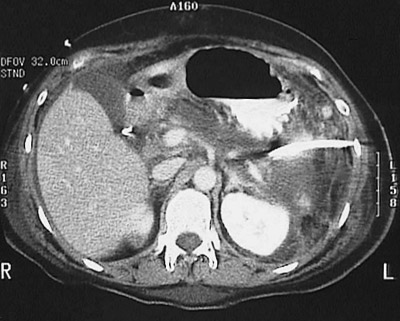

![]() | This CT scan with contrast of the abdomen reveals acute pancreatitis with decreased enhancement of the swollen pancreas from edema, hemorrhage, and fat necrosis. A percutaneous drain has been placed into the tail of the pancreas. A bright vascular clip is present in the region where the gallbladder was previously surgically removed. |